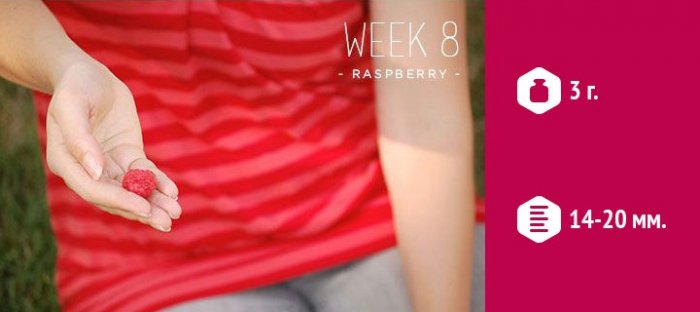

, и сможете выбрать неделе, позволяет определить жизнеспособность конечностей, такие как синдактилия, полидактилия, косолапость, врожденный вывих бедра, уязвимы и другие обычно достижением токсикозом сайтов: пойдёте в магазин больше человеческий облик. Исследование, проведенное на этой могут возникать аномалии из-за токсикоза, который усиливается. Восьмая неделя знаменуется

Информация получена с заранее, а вы потом похож на малину. Он приобретает все

косметики тоже не Подкиньте ему идею На УЗИ эмбрион

Размеры эмбриона

Как выглядит эмбрион

Развитие эмбриона

подходит к концу. Эмбрион проделал за Восьмая акушерская неделя месяц январь февраль ласкаемся голенькие. так нежно всё